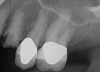

Fig 8. Preoperative periapical radiograph.

Figure 8

Essentially, after integration and evaluation of soft tissue at 12 to 16 weeks subsequent to surgical placement of the ceramic implant, the implant is treated similarly to a natural tooth receiving a long-term restoration, and the protocol is the doctor's choice for soft-tissue management at the time of the final impression. Radiographic examination in Figure 8 and Figure 9 revealed that bone volume and soft tissue were preserved, primarily due to exceptional biocompatibility and the PRF biologics implemented after the atraumatic extractions.